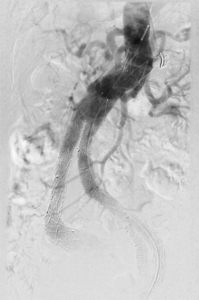

Behandlung der eingeengten Halsschlagader:

Patienten mit hochgradigen arteriosklerotischen Einengungen der Halsschlagader mit oder ohne Symptome eines Schlaganfalles, können neben der operativen Behandlung auch interventionell behandelt werden. Dazu wird ein Stent in die eingeengte Arterie eingesetzt. Ein spezielles Filtersystem verhindert dabei das Verschleppen von Wandablagerungen in die Hirnarterien und damit die Gefahr einer während der Behandlung auftretenden Durchblutungsstörung des Gehirnes.